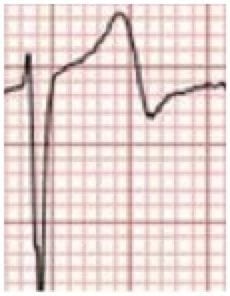

The monitor shows intermittent runs of a broad complex rhythm. His ECG is shown:

The ECG shows sinus rhythm with rate-dependent left bundle-branch block.

The first eight QRS complexes show:

- Sinus rhythm at around 82 bpm

- Normal PR interval (160ms)

- Broad complexes (120ms)

- Typical LBBB morphology (leftward axis, deep S-wave in V1, broad ‘M’ pattern in I, aVL)

The remainder of the ECG shows:

- Slowing of the sinus rate to 60bpm

- Narrowing of the QRS complexes to 80ms

- Disappearance of the LBBB pattern

The appearance in the chest leads is suggestive of Wellens syndrome, with:

- Deep T wave inversions in the right- and mid-precordial leads (V1-4)

- Biphasic T wave morphology in V2

There is also subtle T wave flattening and ST depression in the last four complexes of the lead II rhythm strip, indicating possible inferior ischaemia.